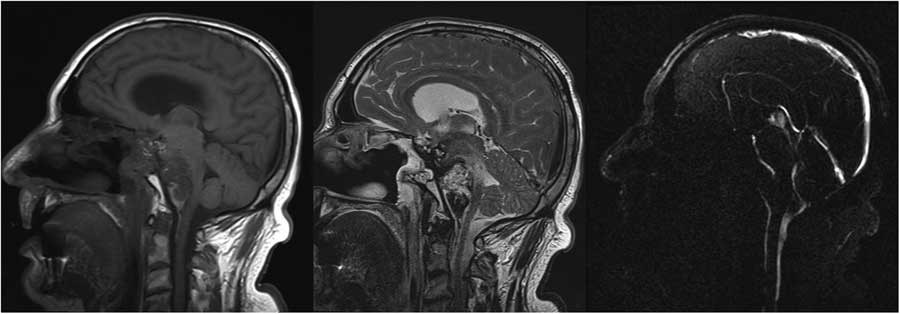

The patient remained free of recurrence until 1 year after his third operation. At that time radiologic recurrence was noted with only minor symptoms. After 6 months, the patient developed lower cranial nerve deficits including swallowing issues and drop attacks. An attempt at surgical decompression was undertaken via a retrosigmoidal approach, but the tumor had become too adherent to the brainstem, extending from the prepontine cistern into the belly of the pons with cystic component (Figure 1), with adjacent signal changes on FLAIR and T2 images. Diffusion weighted imaging showed some areas of restriction suggestive of infarction. The patient passed away during admission, likely from brainstem perforator infarct (Figures 2-4).

Figure 3 Sagittal T1, T2 and PC in plane flow magnetic resonance images demonstrating pontine infiltration of the tumor and compression of the basilar artery.